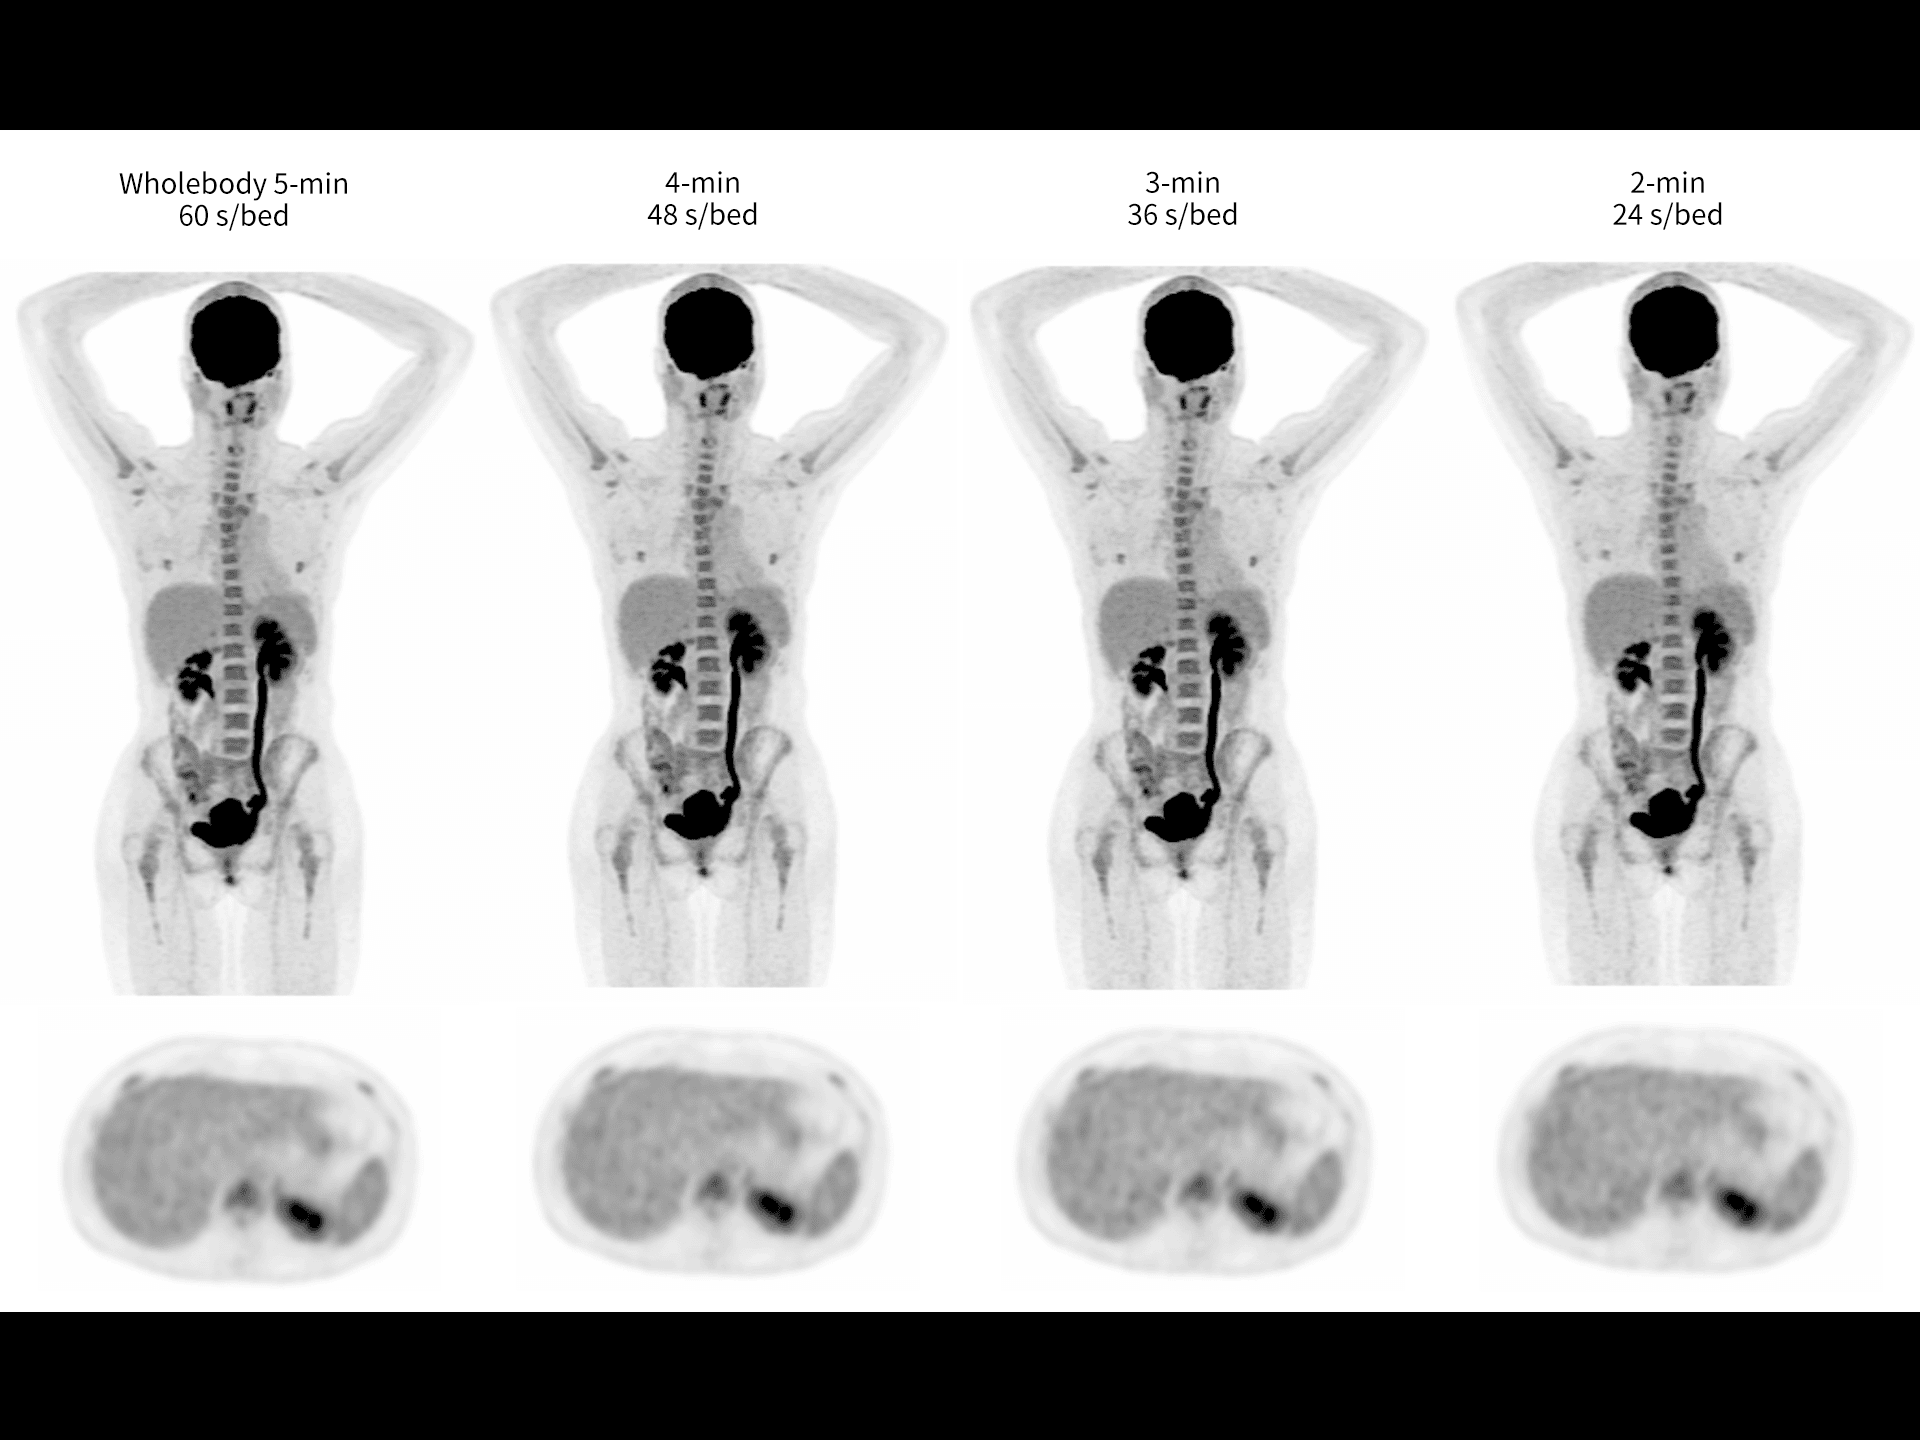

Imagistică total-body în 10 minute, cu doză redusă

Scanări PET/CT eficiente, cu expunere minimă pentru pacient.

Imagistică whole-body rapidă, în doar 2 minute

Performanță clinică de top, cu timp redus de examinare.